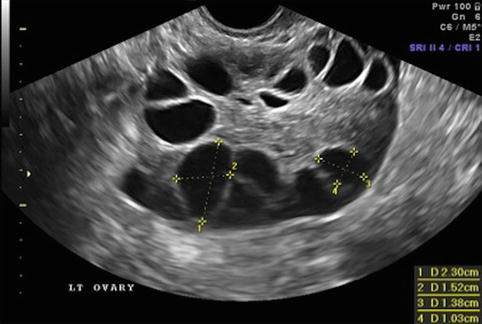

We determine that follicles of 12 19 mm on the day of trigger administration had the greatest contribution to the number of oocytes. This will have a successful ovulation. 15 10 mm and 10 9 mm and right ovary has multiple small follicles with no dominat follicle. Each additional millimeter of endometrial thickness increased the optimal follicular size by 0 5 mm.

The enlargement of the 3 to 5 mm follicle pool could be due to the atretic follicles since the number of 6 to 7 mm follicles decreased. It will then grow 2 to 3 mm in size each day. 15 11 mm and 9 10 mm follicles and right has same. Follicle sizes don t determine whether the egg is mature or not.